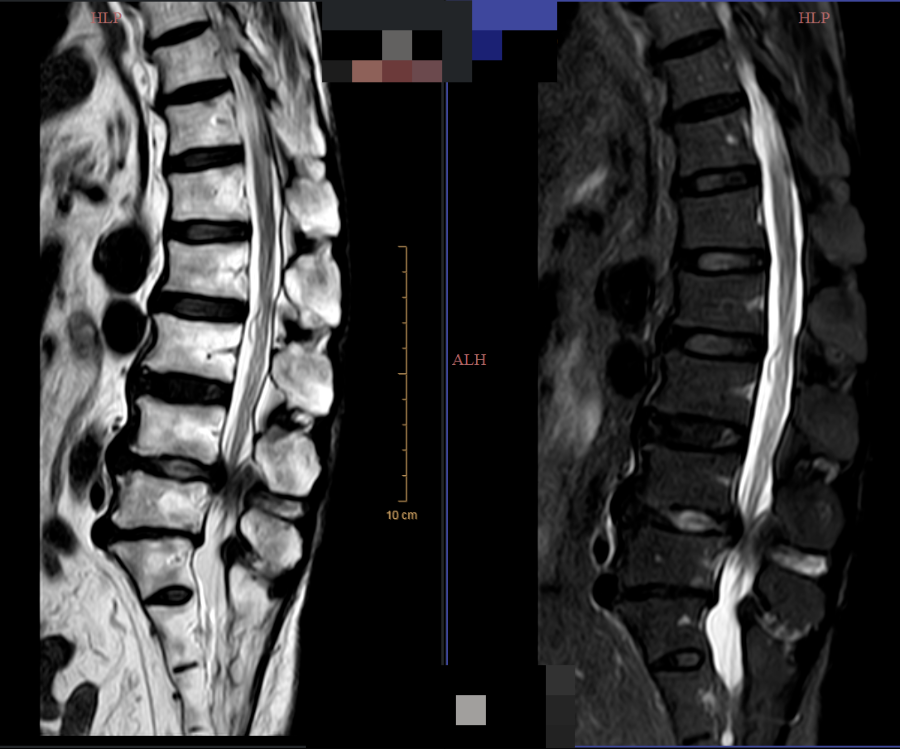

术前

胡奶奶虽然高龄,但身体尚健,被腰椎间盘突出症折磨了二十余年,近期疼痛加剧伴行走困难。经我院骨一科团队详细评估,为其采用了经皮射频热凝联合胶原酶化学溶解术。该微创方案无需开刀,仅通过穿刺针操作,利用射频热凝精准阻断疼痛信号,同时于硬膜外前间隙即盘外注入胶原酶溶解突出髓核,从根源解除神经压迫。